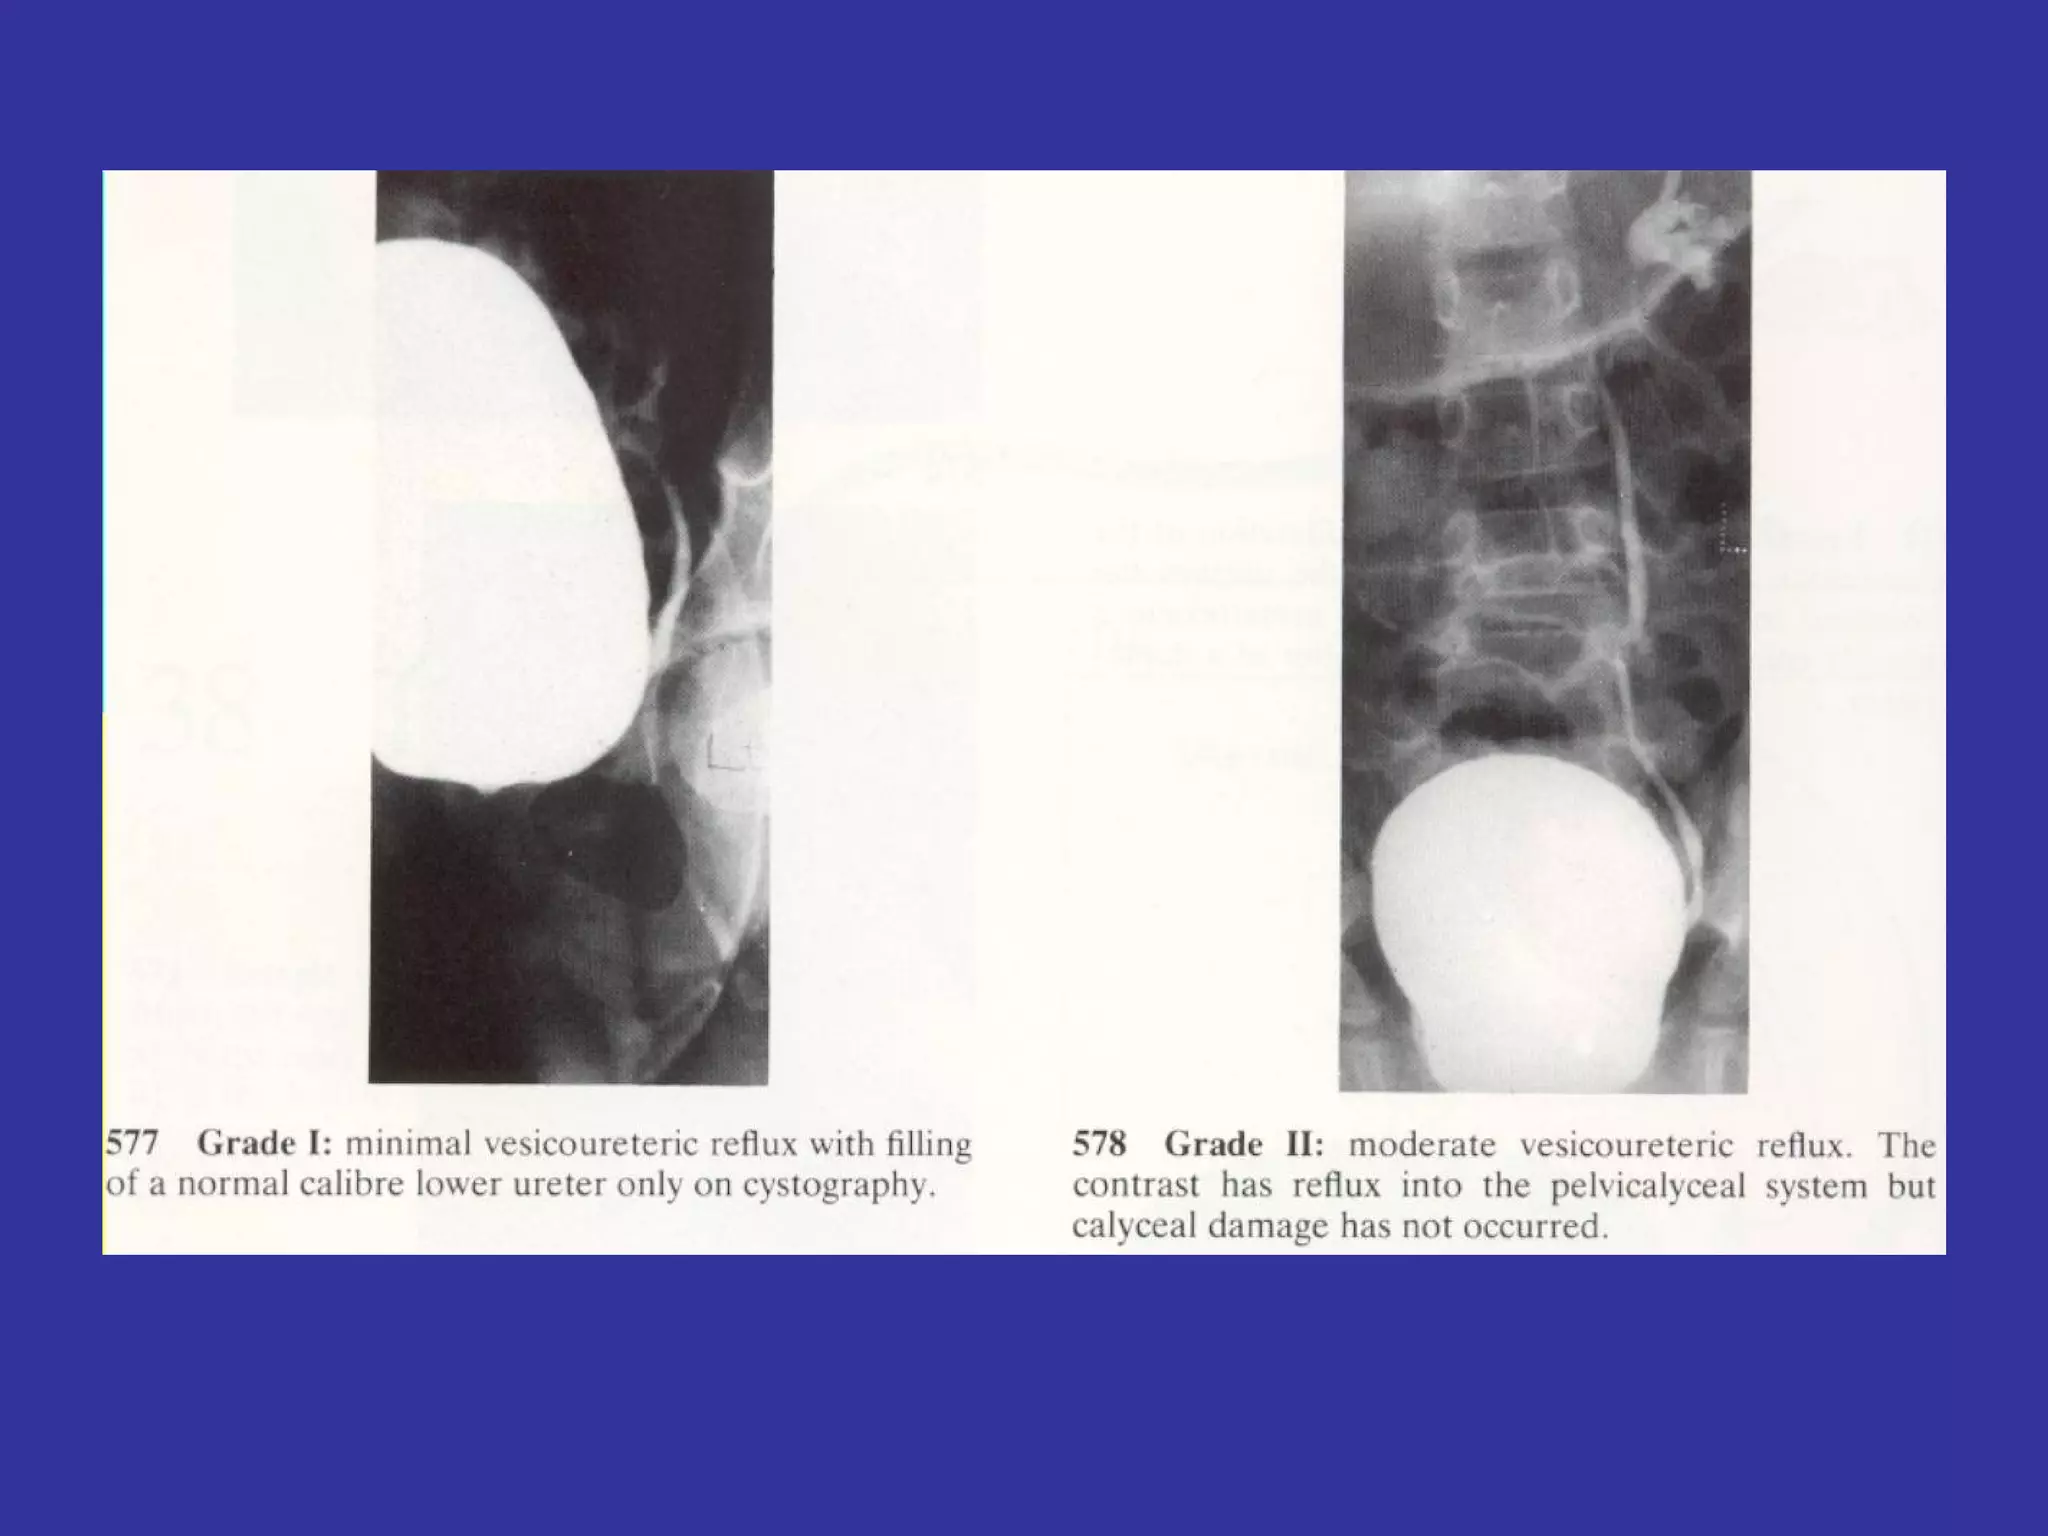

VESICO-URETHERAL REFLUX Is the passage of urine from the bladder to the renal pelvis, secondary to an incompetent  valvular mechanism at the uretero-vesical junction Epidemiology:   Family factors- 34% found to have VUR.  Classification:  REFLUX: Grade  I-   Into a non-dilated distal ureter Grade II-   Into the upper collecting system, with normal calyceal  and no dilatation Grade III-  Mildly dilated/tortuous ureter, with mild blunting of calyceal  Grade IV-  Grossly dilated ureter, moderate dilatation/tortuosity of ureter.  Grade V-   Massive reflux with gross ureteral dilatation and tortuosity of ureter S/S:   UTI sx,  HTN,  Abdominal mass secondary,  Hydronephrosis,  FTT, Enuresis LAB:   Voiding cystourethrogram (VCUG)-  Gold  standard Renal U/S- detects hydronephrosis DMSA renal scan- detects renal  scarring DMSA: Dimercaptosuccinic  acid

VESICO-URETHERAL REFLUX Isthe passage of urine from the bladder to the renal pelvis, secondary to an incompetent valvular mechanism at the uretero-vesical junction Epidemiology: Family factors- 34% found to have VUR. Classification: REFLUX: Grade I- Into a non-dilated distal ureter Grade II- Into the upper collecting system, with normal calyceal and no dilatation Grade III- Mildly dilated/tortuous ureter, with mild blunting of calyceal Grade IV- Grossly dilated ureter, moderate dilatation/tortuosity of ureter. Grade V- Massive reflux with gross ureteral dilatation and tortuosity of ureter S/S: UTI sx, HTN, Abdominal mass secondary, Hydronephrosis, FTT, Enuresis LAB: Voiding cystourethrogram (VCUG)- Gold standard Renal U/S- detects hydronephrosis DMSA renal scan- detects renal scarring DMSA: Dimercaptosuccinic acid